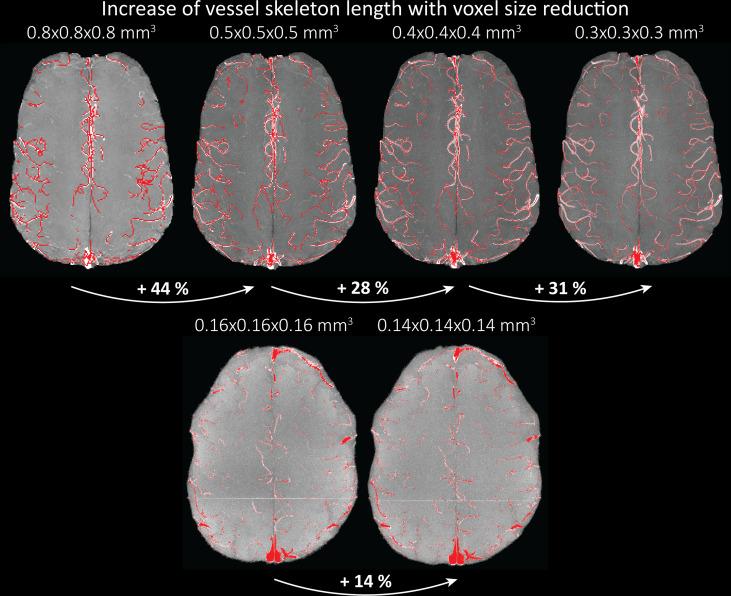

The pial arterial vasculature of the human brain is the only blood supply to the neocortex, but quantitative data on the morphology and topology of these mesoscopic arteries (diameter 50-300 µm) remains scarce. Because it is commonly assumed that blood flow velocities in these vessels are prohibitively slow, non-invasive time-of-flight magnetic resonance angiography (TOF-MRA)-which is well suited to high 3D imaging resolutions-has not been applied to imaging the pial arteries. Here, we provide a theoretical framework that outlines how TOF-MRA can visualize small pial arteries in vivo, by employing extremely small voxels at the size of individual vessels. We then provide evidence for this theory by imaging the pial arteries at 140 µm isotropic resolution using a 7 Tesla (T) magnetic resonance imaging (MRI) scanner and prospective motion correction, and show that pial arteries one voxel width in diameter can be detected. We conclude that imaging pial arteries is not limited by slow blood flow, but instead by achievable image resolution. This study represents the first targeted, comprehensive account of imaging pial arteries in vivo in the human brain. This ultra-high-resolution angiography will enable the characterization of pial vascular anatomy across the brain to investigate patterns of blood supply and relationships between vascular and functional architecture.

人脑的脑膜动脉血管是新皮质的唯一血液供应,但这些中观动脉(直径 50-300μm)的形态和拓扑结构的定量数据仍然很少。由于通常假设这些血管中的血流速度非常缓慢,因此不适合进行非侵入性的时间飞跃磁共振血管造影术(TOF-MRA)-这种技术非常适合高 3D 成像分辨率-尚未应用于脑膜动脉成像。在这里,我们提供了一个理论框架,概述了如何通过使用单个血管大小的极小体素来可视化体内的小脑膜动脉。然后,我们通过在 7 特斯拉(T)磁共振成像(MRI)扫描仪上使用 140μm 各向同性分辨率和前瞻性运动校正来对脑膜动脉进行成像,并提供了这一理论的证据,表明可以检测到直径为一个体素宽度的脑膜动脉。我们的结论是,脑膜动脉的成像不受血流缓慢的限制,而是受可实现的图像分辨率的限制。这项研究代表了首次在人类大脑中针对脑膜动脉进行体内成像的全面综合描述。这种超高分辨率血管造影术将能够描述整个大脑的脑膜血管解剖结构,以研究血液供应模式和血管与功能结构之间的关系。